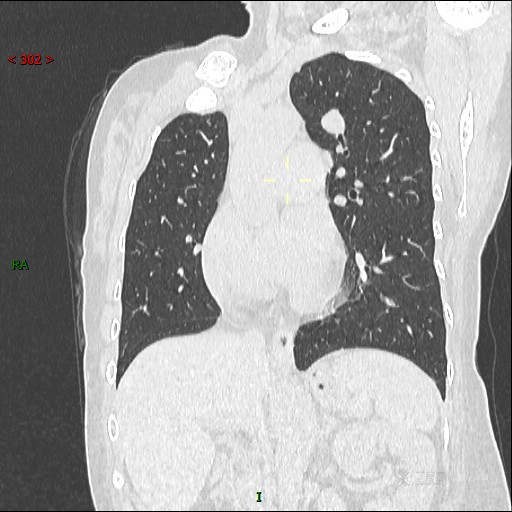

CT值